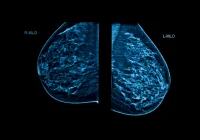

Existing automated segmentation models based on artificial intelligence (AI) have shown promise, but most are trained on healthy individuals or patients with pancreatic tumours. These models often fail when applied to CP patients because of the significant morphological differences. To address this limitation, researchers developed a new AI-based segmentation model trained on a large, mixed dataset that includes both healthy subjects and individuals with CP. The aim was to build a model capable of accurately segmenting the pancreas across a broad spectrum of anatomical variations and imaging conditions.

The AI model was developed using the nnU-Net architecture, a self-configuring deep learning framework known for its versatility in medical image segmentation. The training dataset included 326 CT scans from Aalborg University Hospital in Denmark, comprising both CP patients and healthy controls. These scans represented a wide range of anatomical and pathological presentations. The model was then tested internally on 47 cases from the same hospital and externally on datasets from Bergen Hospital in Norway and the National Institutes of Health (NIH) in the United States.

Performance was evaluated using the Dice score, a standard metric for measuring segmentation accuracy. The model achieved a high Dice score of 0.85 on the internal test set, and consistent scores of 0.79 on both external datasets. These results highlight the model’s robustness and adaptability across different patient populations, scanner models and imaging protocols. Notably, this performance is comparable to, or better than, other leading AI segmentation models trained solely on healthy subjects.